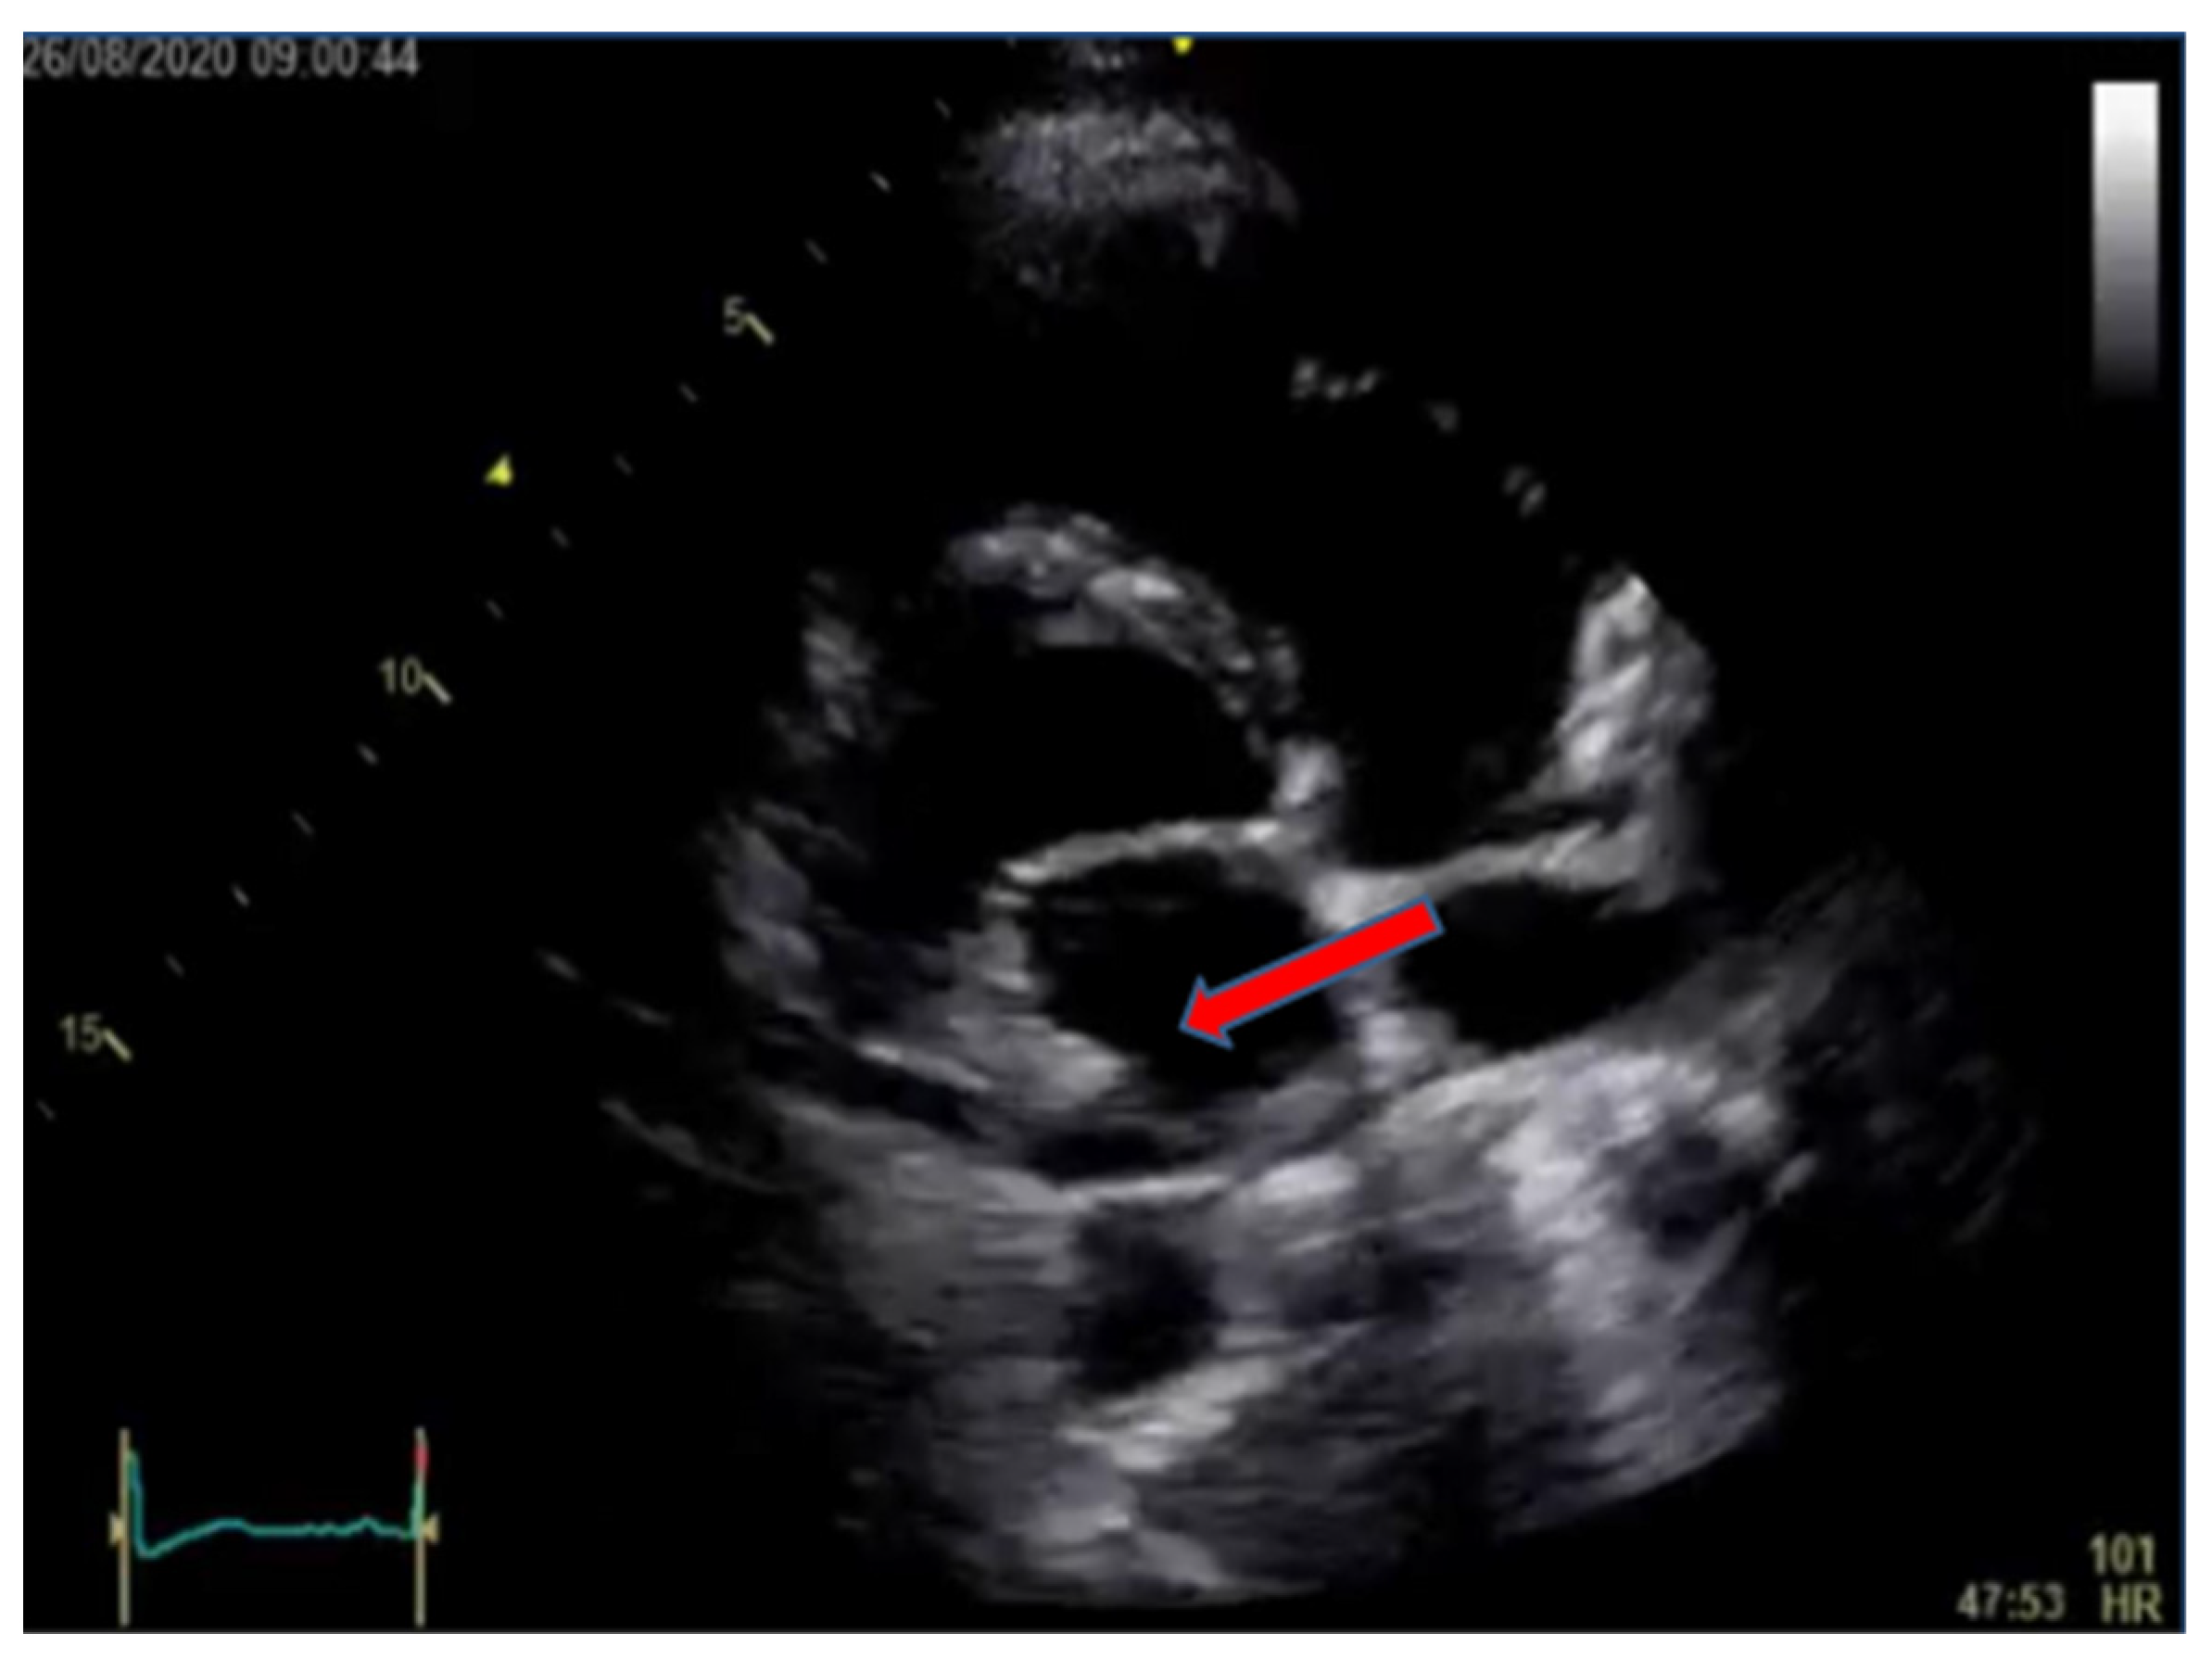

2. Case Presentation